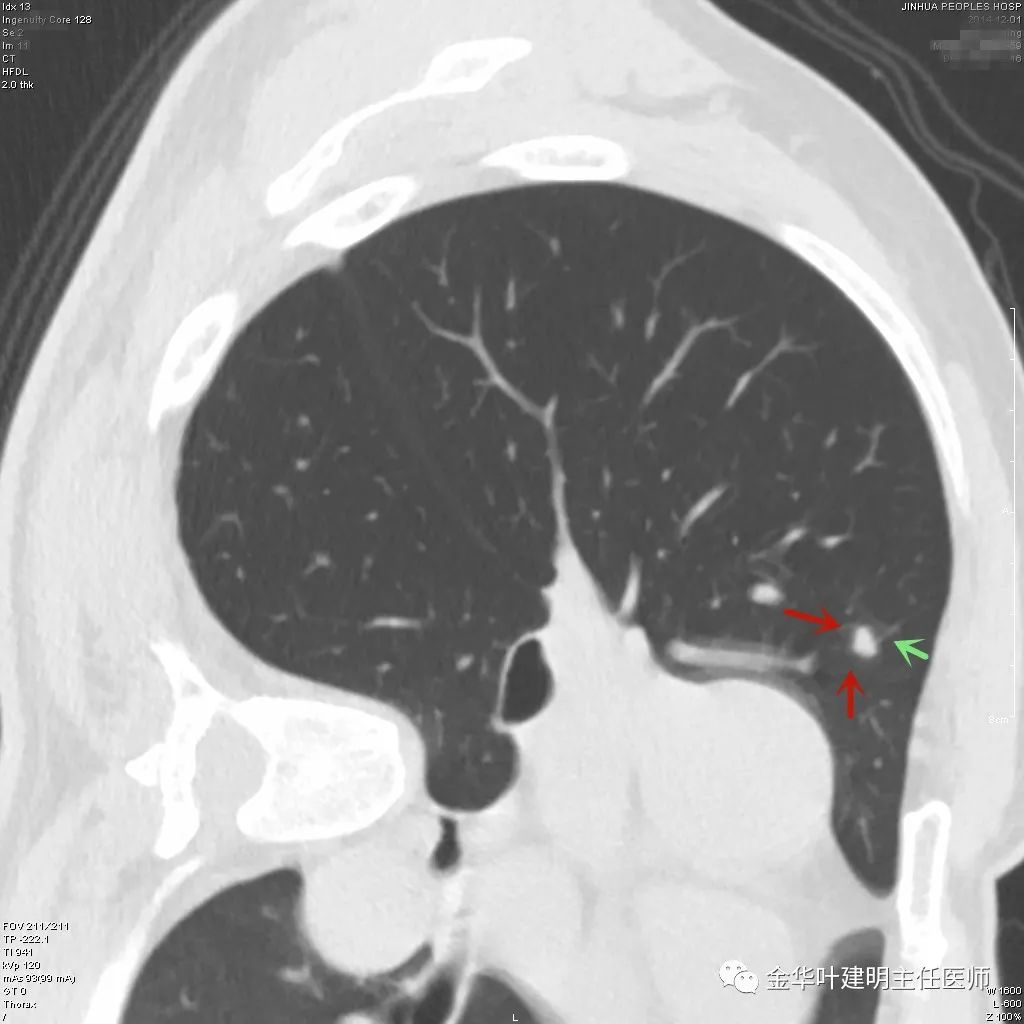

上图示结核。我们发现其有明显的卫星灶,如绿色箭头所示,主病灶处也是周边有模糊区域,病灶整体密度较为均匀(肿瘤容易生长不均致密度欠均匀,显杂乱)。